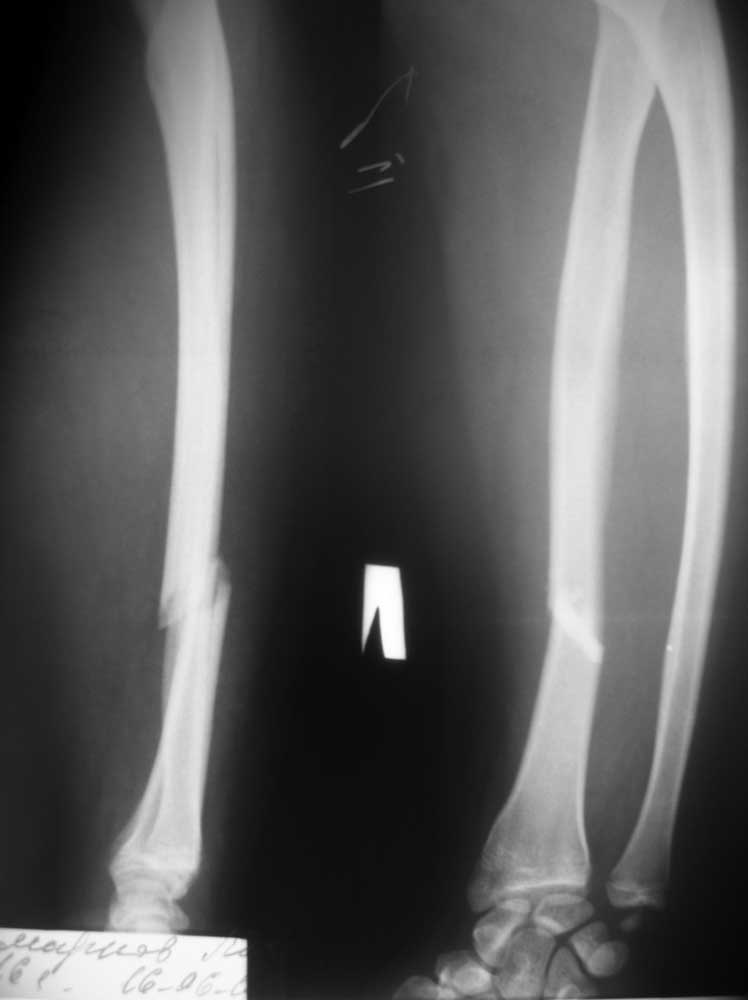

[Ortho] : Перелом костей предплечья

> Пострадавший, 16 лет, поступил в отделение 16.06.12. Травма в результате

> ДТП- воткнулся на

> скутере в неподвижный автомобиль. Других повреждений нет. За прошедшие

> выходные какими-то

> окольными путями умудрился получить консультацию сотрудника института

> травматологии и

> ортопедии, находящегося в областном центре. Сотрудник этот (д.м.н.,

> профессор, весьма

> уважаемый в травматологическом, да и вообще во врачебном, сообществе

> нашего региона

> человек) рекомендовал консервативное лечение. Сам пострадавший, точнее,

> его родители,

> хотят отличного результата, отсутствие последствий, независимо от метода

> лечения, но

> находятся под влиянием слов профессора. Считаю, что такое повреждение

> просто необходимо

> оперировать, но чтобы переубедить пострадавшего, необходимо авторитетное

> мнение

> уважаемого сообщества. PS. Если операция, то может быть есть какие-то

> особенности. Заранее

> благодарен всем, высказавшим свое мнение. Любое!